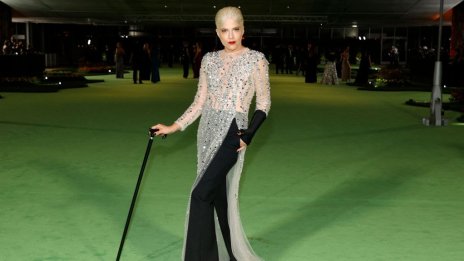

Селма Блеър след трансплантация на стволови клетки: Чувствам се като нов човек

Актрисата говори за борбата си с множествената склероза

Селма Блеър победоносно: Множествената ми склероза е в ремисия

Актрисата сподели, че трансплантацията на стволови клетки е спасила живота й